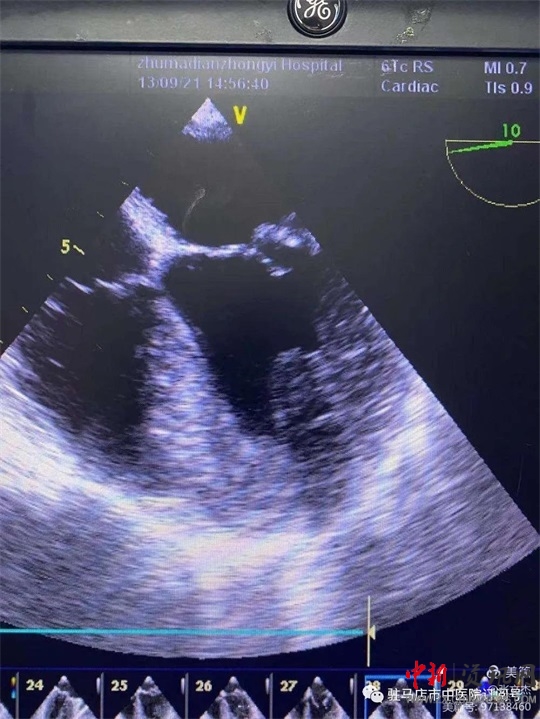

術(shù)前經(jīng)食道心臟超聲

復(fù)跳后經(jīng)食道心臟超聲,二尖瓣功能較術(shù)前明顯改善。